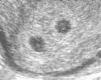

After 10 weeks of gestation chorionicity is determined by the evaluation of the number of the placental masses and, in case of a single placental mass, by the characteristics of the membrane dividing the amniotic sacs. In dichorionic twins with fused placentas, amnios and chorion reflect away from the placental surface, creating a potential space into which villi can grow. Sonographically this space appears as a triangular-shaped extension of placental tissue into the base on the inter-twin membrane. This sign was first described in 1981 as the “lambda” sign11 and is used interchangeably with the “twin peak” sign described in 199212 (Fig. 4). In monochorionic pregnancy there is a single layer of continuous chorion limiting the villous growth; the intertwin membrane takes off perpendicularly to the placental surface producing the sonographic sign known as “T” sign (Fig. 5).